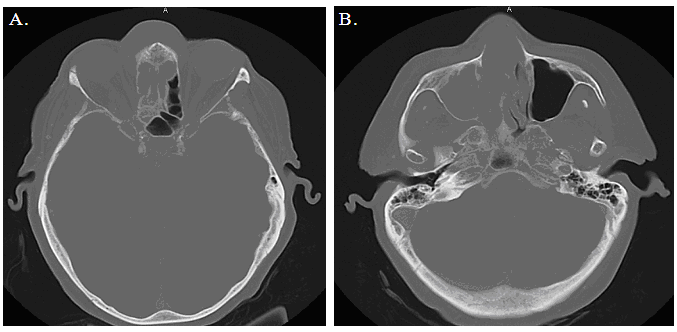

Pathologically, a preliminary diagnosis of lymphoma was made and the patient underwent urgent imaging for staging (figure 1). Treatment for diffuse large B-cell lymphoma, the final pathologic diagnosis, with rituximab plus cyclophosphamide/vincristine/ prednisone (R/CVP) was then initiated within the week by a hematologist-oncologist.

Figure 1: Axial unenhanced CT scan showing; A) a large sinonasal tumor with extranasal spread and bilateral orbital involvement, and B) sinonasal tumor filling the nasal cavity with destruction of the nasal septum and medial wall of the maxillary sinus.